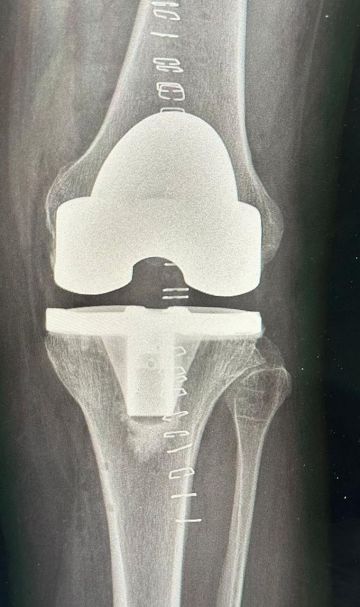

تمكن الفريق الطبي في مستشفى الدرعية، عضو تجمع الرياض الصحي الثالث، من إجراء عملية ناجحة لاستبدال مفصل الركبة اليسرى بتقنية الروبوت، بقيادة الطبيب الزائر د. فوزي الجاسر، بروفيسور جراحة العظام واستشاري تبديل المفاصل والأورام.

وبعد التقييم الدقيق، أُجريت العملية باستخدام الروبوت الجراحي لإزالة الاحتكاك وتعديل الانحراف وتركيب المفصل بالتقنية الحديثة، مما أسهم في تخفيف الألم واستعادة القدرة على الحركة وثني الركبة بشكل طبيعي.